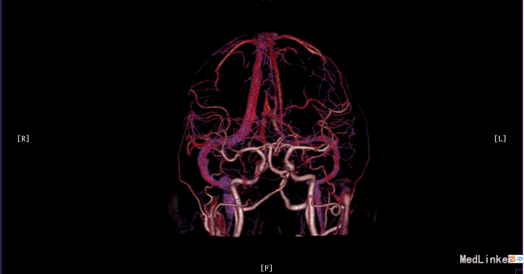

入院体检:T 36.9°C,P 87次/分,R 22次/分,BP 136/69mmHg。全身皮肤无黄染及出血点,全身浅表淋巴结未扪及肿大。双肺呼吸音清,未闻及干湿性罗音。心率87bpm,律齐,各瓣膜听诊区未闻及杂音。腹平,腹肌软,肝脾肋下未及,无压痛、反跳痛,肠鸣音正常。脊柱四肢无畸形,双下肢无水肿。神经系统:神清语晰,对答切题,记忆力、定向力、计算力正常,查体合作。双侧瞳孔等圆等大,直径约3mm,对光反射灵敏,双眼球活动自如,未见眼震。双侧额纹对称,双侧鼻唇沟对称,伸舌居中。四肢肌张力正常,左侧肢体肌力II级,指鼻试验、跟膝胫试验、闭目难立征未能配合检查。双侧腱反射对称存在,双侧巴氏征未引出。颈软,双侧克氏征、布氏征(-)。 辅助检查:生化:超敏C反应蛋白:2.6mg /l、乳酸脱氢酶(LDH):105U/L、甘油三酯(TG):2.32mmol/L、尿酸(URIC):416umol/L;同型半胱氨酸:14.3umol /l;D-二聚体定量:270ng /ml;糖化血红蛋白(HbA1c):5.1%;红细胞沉降率:3mm/h;人脂蛋白相关磷脂酶A2:378ng /ml;风湿十二项:(-); 胸部DR:主动脉硬化,双肺未见异常。心脏彩超:LVEF:66%。心内结构未见异常。 心内未见异常血流。 左室舒张功能降低。颈血管彩超:双侧颈总动脉、颈内动脉、颈外动脉、椎动脉未见异常。 双侧颈动脉、椎动脉血流速度正常。 急诊CT未见明显异常。 头颅MR:1、 双侧额叶软化灶,病灶周边少许胶质增生;2、MRA示未见明显异常。 头颅CTA:双侧颈内动脉虹吸段、双侧大脑中动脉、双侧大脑前动脉及其分支管壁尚规则,管腔通畅未见明显狭窄;右侧椎动脉颅内段管腔较左侧稍细小,余椎动脉、基底动脉及双侧大脑后动脉管腔未见明显变窄。大脑willis动脉环清晰显示,未见明显异常。 头颅CTV:大脑静脉系统上矢状窦、窦汇、横窦、乙状窦、直窦、大脑大静脉和颈内静脉管壁规则,管腔通畅未见狭窄、畸形等异常。 动态心电图示:1.窦性心动过缓;2.偶发室性早搏;3.偶发房性早搏;4.提示不完全性右束支阻滞;5.T波改变(心率快时);6.心率变异性:正常。 脑电图无异常。